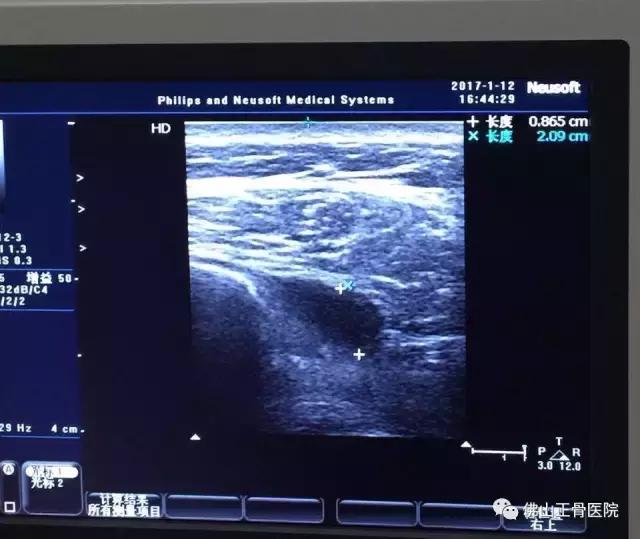

原来困扰刘女士的症状为左肩袖损伤。在超声仪器下,曾主任看见了刘女士肩膀下面的肌腱撕裂和积液,确诊病因后,他随即为刘女士做了超声介导下注射治疗。后经综合治疗2周后,刘女士左肩疼痛基本改善,穿衣等日常活动也恢复正常。

患者也可直观地看到动态治疗效果

动态超声图像:

超声不仅可对一个关节进行360度扫查,而且超声的实时性使得其能够观察肌肉、肌腱、外周神经、关节等的运动情况,这些信息是其他影像学检查所无法了解到的。因此超声可实时动态观察病灶在运动状态下的某些特征性表现,从而确诊某些疾病。如肩峰下撞击综合征。